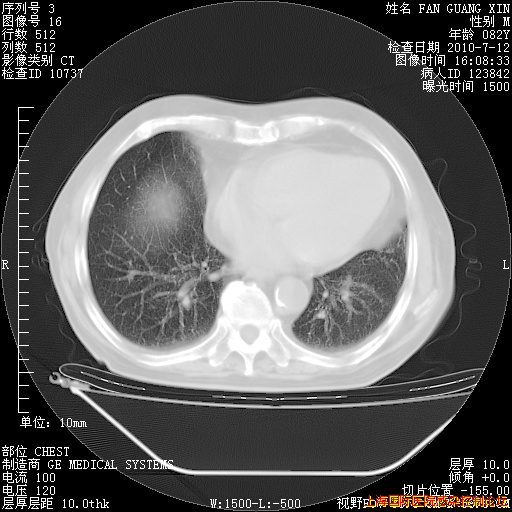

补发6月12日肺部CT肺窗

6月12日肺窗